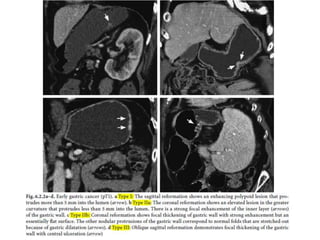

hemidiaphragm. Acute gastric dilatation after trauma

Complication of endoscopy.

A linear collection of intramural gas surrounds

the stomach